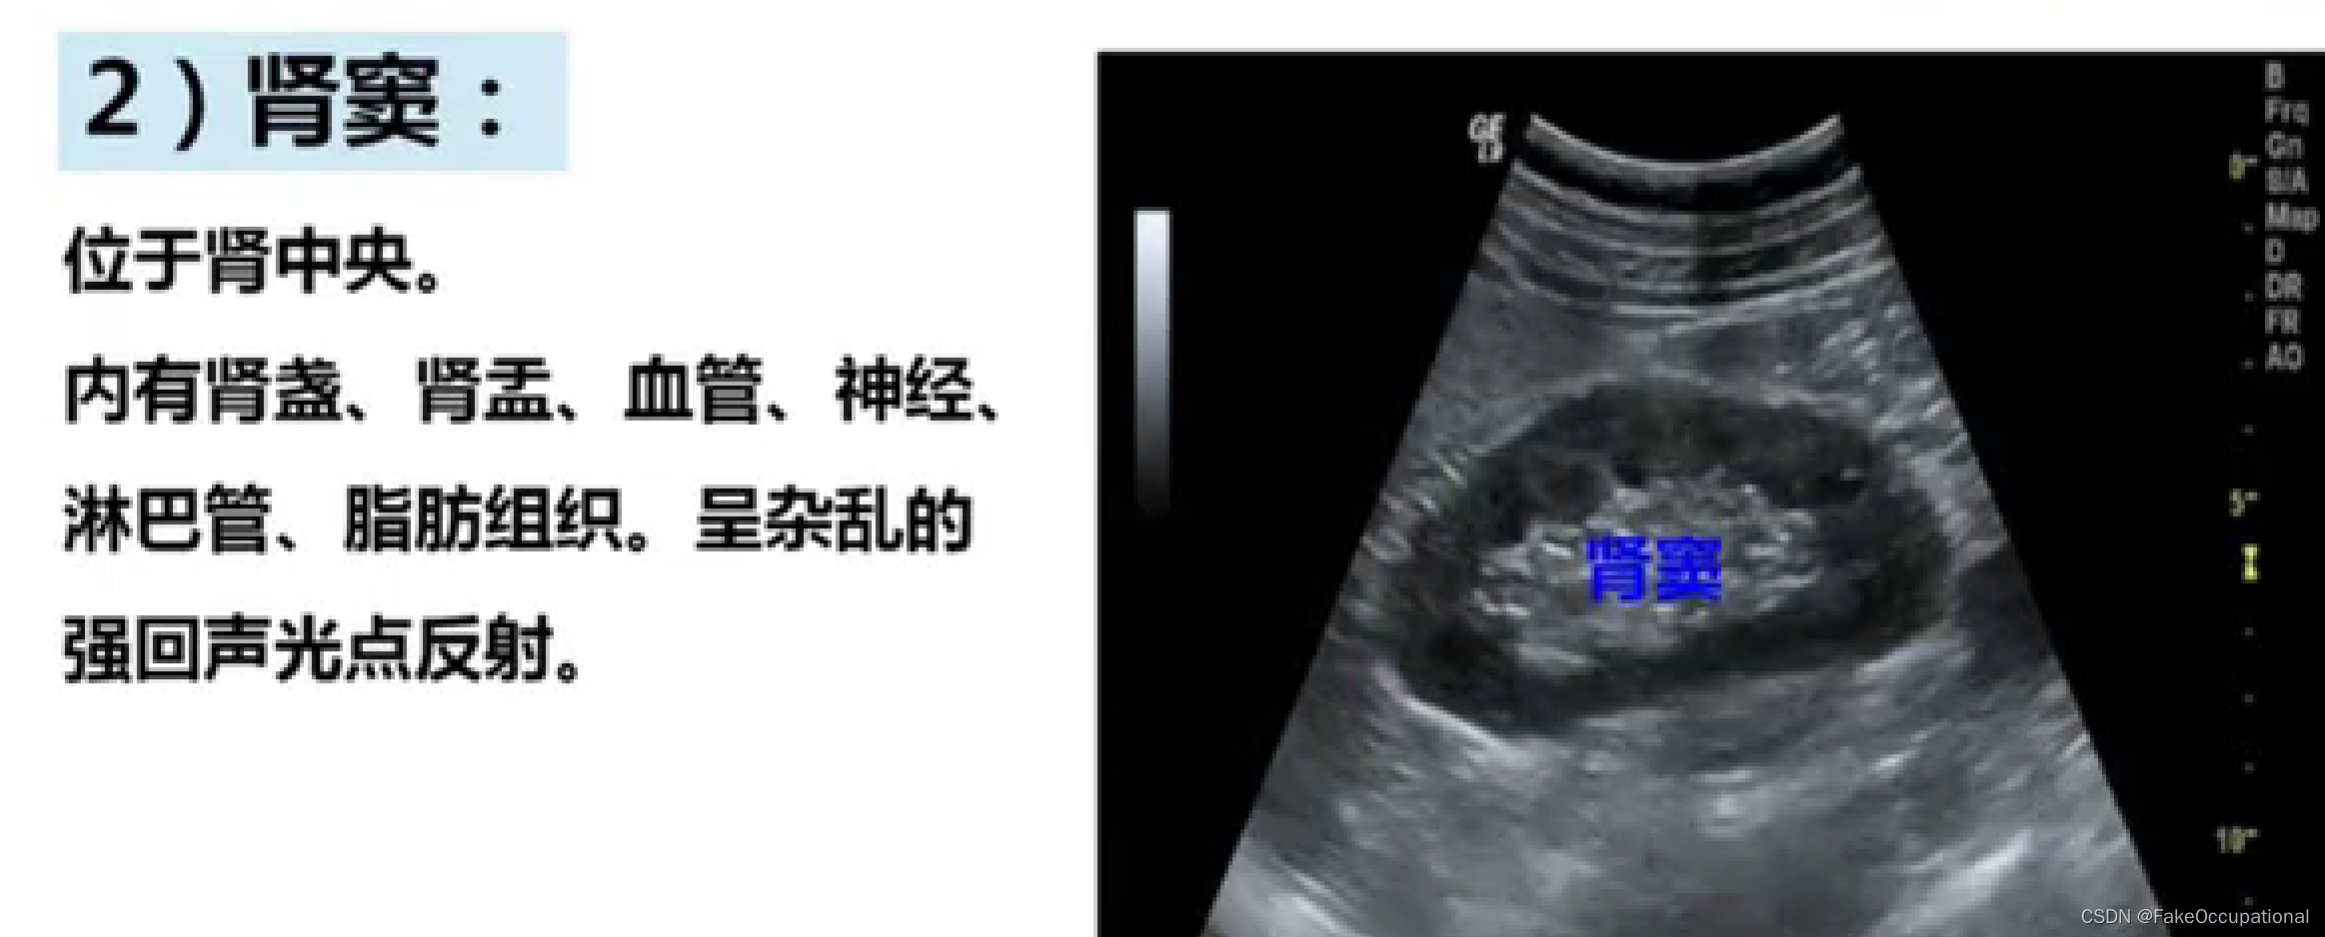

正常肾脏及肾血管超声表现